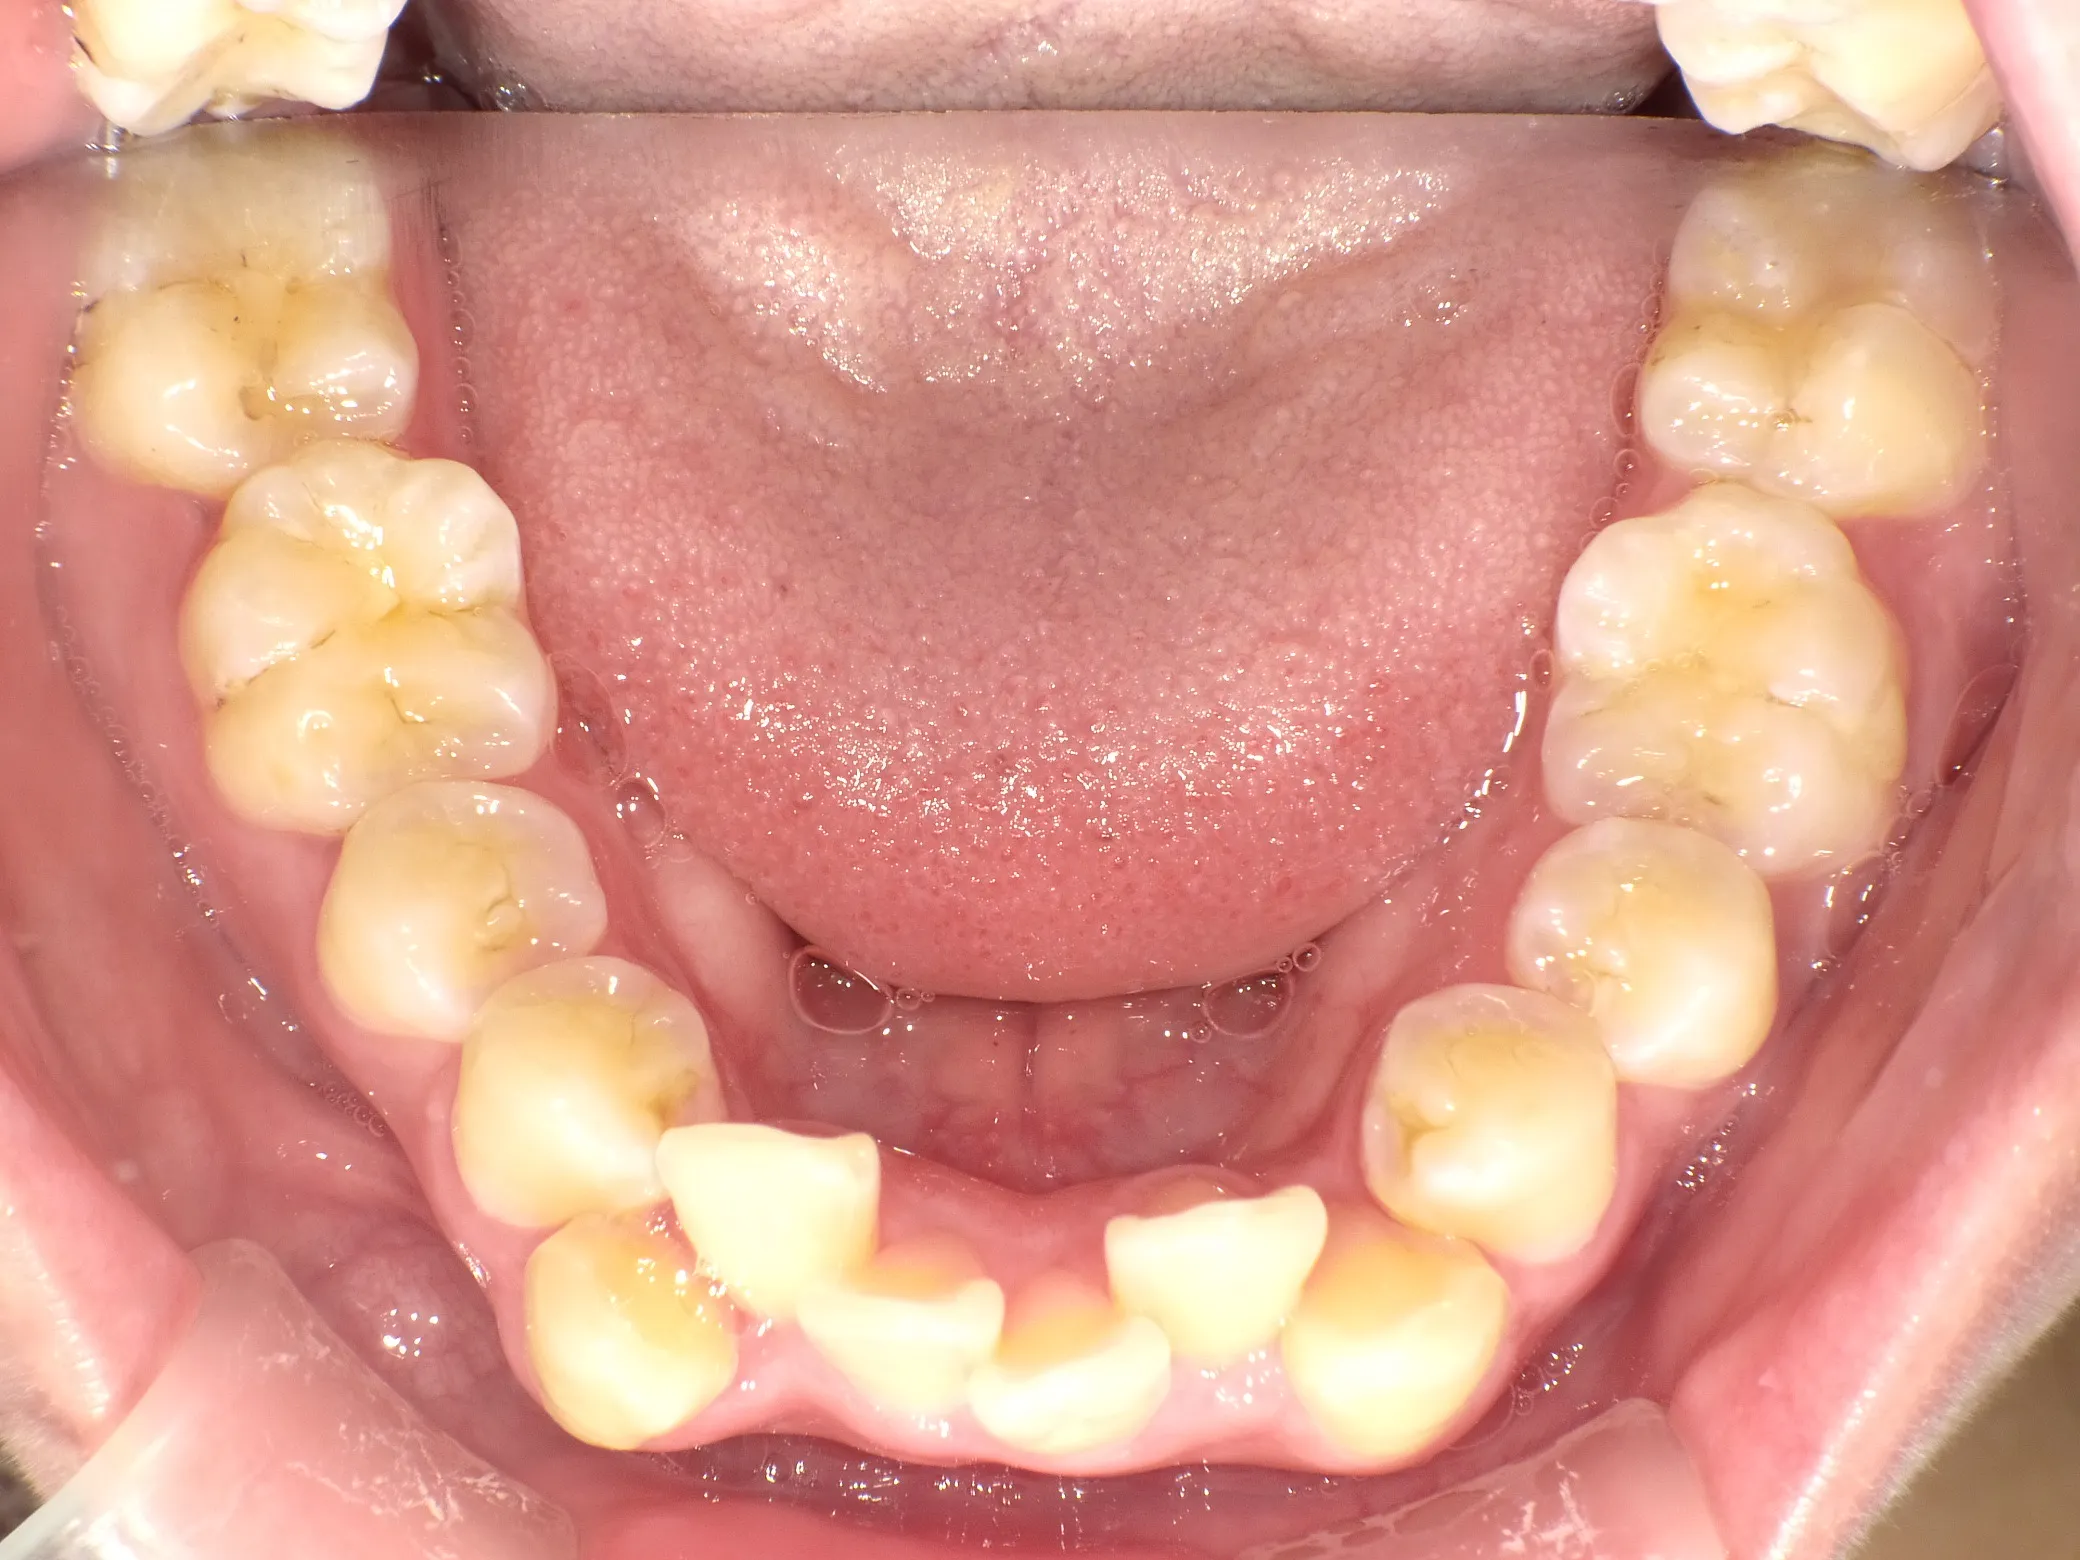

症例④

症例4_治療前 症例4_治療後

年齢・性別 24才男性

治療方法 ホワイトブラケット

治療期間 3年

治療総額 850,000円

特記事項 抜歯あり

リスク・副作用 治療の初期段階では痛みや不快感が生じやすくなりますが、1週間前後で慣れます